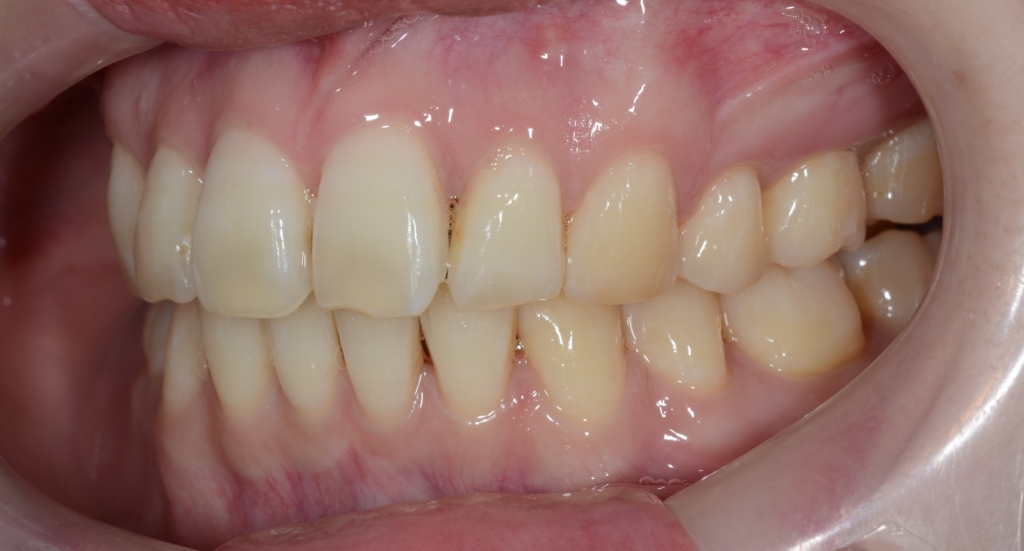

【診断】

#1.上顎前突

#2.顎と歯の大きさの不調和による叢生

#3.ガミースマイル

と診断しました。

*歯並びの写真で見ると「出っ歯」であるとは分かり難いですが、頭部全体のレントゲン写真を見ると、出っ歯であることがハッキリと分かります。

【治療方針】

1.上下左右の奥歯を抜歯をしてスペースを作り、前歯の乱れをきれいにする

2.アンカースクリューを用いて、上顎前歯を圧下させてガミースマイルの改善を図る

3.並行して、下の前歯を最大限に後方へ移動

4.その後、上の前歯を残る隙間分最大限に引っ込める

5.必要ならアンカースクリューを追加して上の歯列をより後方へ引っ込める

という治療計画にて、矯正を進めることにしました。